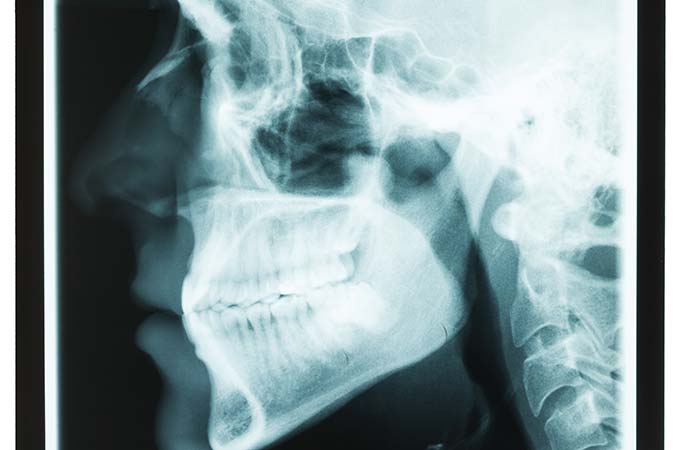

dental patient in need of tmj treatment

Temporomandibular joint disorders may be the cause